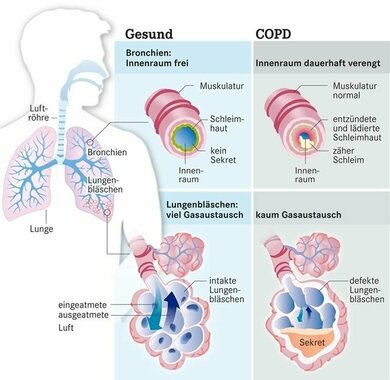

Der Begriff COPD fasst mehrere Varianten der Lungenerkrankung zusammen. Betroffen sind die unteren Atemwege, also die Bronchien und die noch kleineren Bronchiolen. Dort kommt es zu einer anhaltenden Entzündung, einer chronischen Bronchitis. Die Bronchien verengen sich aufgrund von Umbauprozessen dauerhaft. Deshalb vermindert sich der Atemluftstrom, was eine Atemnot verursacht.

Bei einem Teil der Patienten dominiert diese Entzündung. Bei einem anderen greift die Krankheit zusätzlich die Lungenbläschen (siehe Grafik) an. Deren Aufgabe ist es, Sauerstoff aus der Atemluft ins Blut zu schleusen und das Stoffwechselprodukt Kohlendioxid in die Atemluft abzugeben. Bei einer COPD zerfallen die Wände der Lungenbläschen, sie platzen sozusagen. Die Fläche für den Gasaustausch verkleinert sich. Er funktioniert immer schlechter. Ein Sauerstoffmangel entsteht, obgleich die Lunge voller Luft ist. Der Fachbegriff lautet Lungenemphysem.

Eine COPD kann Bronchien und Lungenbläschen betreffen

© W&B/Dr. Ulrike Möhle